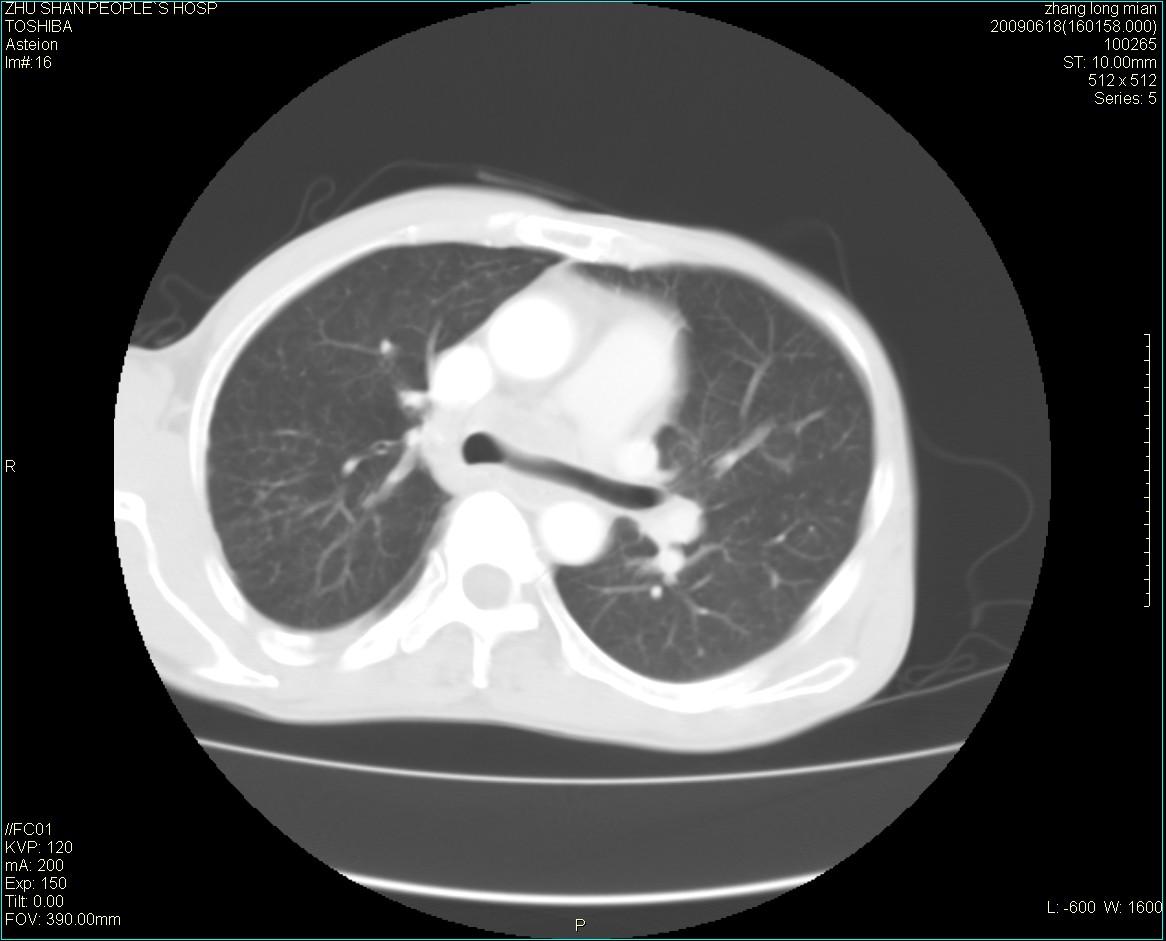

男性 65岁 胸片发现右下肺包块.诊断肺ca并纵隔转移没有问题吧!

两侧胸廓不对称,右侧呈塌陷改变,右肺萎缩。

右下肺见浅分叶状软组织块影,边缘有毛刺,其下部似见不完整偏心空洞影,邻近胸膜凹陷征,并胸腔积液。

增强见纵隔区气管隆突上下及左肺门区肿大淋巴结。左肺感染性病灶。

另见右上肺见一枚小结节影,性质待定。